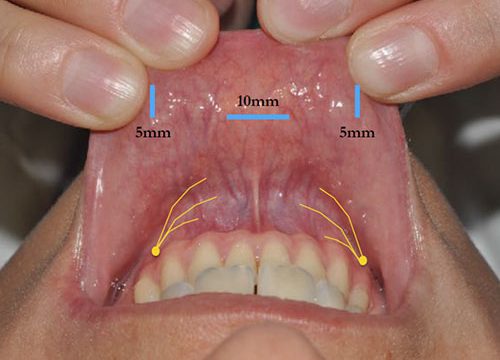

Dla Pań, które nie chcą mieć blizny na szyi po operacji tarczycy oferujemy operację tarczycy techniką endoskopowego wycięcia tarczycy z dostępu przez przedsionek jamy ustnej (ang.TransOral Endoscopic Thyroidectomy by Vestibular Approach – TOETVA) przy użyciu neuromonitora. W technice TOETVA dostęp operacyjny do tarczycy następuje nie jak w klasycznej chirurgii tarczycy poprzez wykonanie cięcia w dolnej części szyi lecz małoinwazyjnymi metodami endoskopowymi przez przedsionek jamy ustnej po założeniu trzech trokarów: jednego o średnicy 10mm oraz dwóch o średnicy 5mm, co pozwala na uniknięcie cięcia na skórze szyi i uzyskanie dobrego efektu kosmetycznego po operacji wynikającego z braku blizny na skórze szyi. Niewielkie rany po trokarach w obrębie przedsionka jamy ustnej szybko się goją z dobrym efektem kosmetycznym. Zabiegi operacyjne realizuje prof. Marcin Barczyński wraz z zespołem.